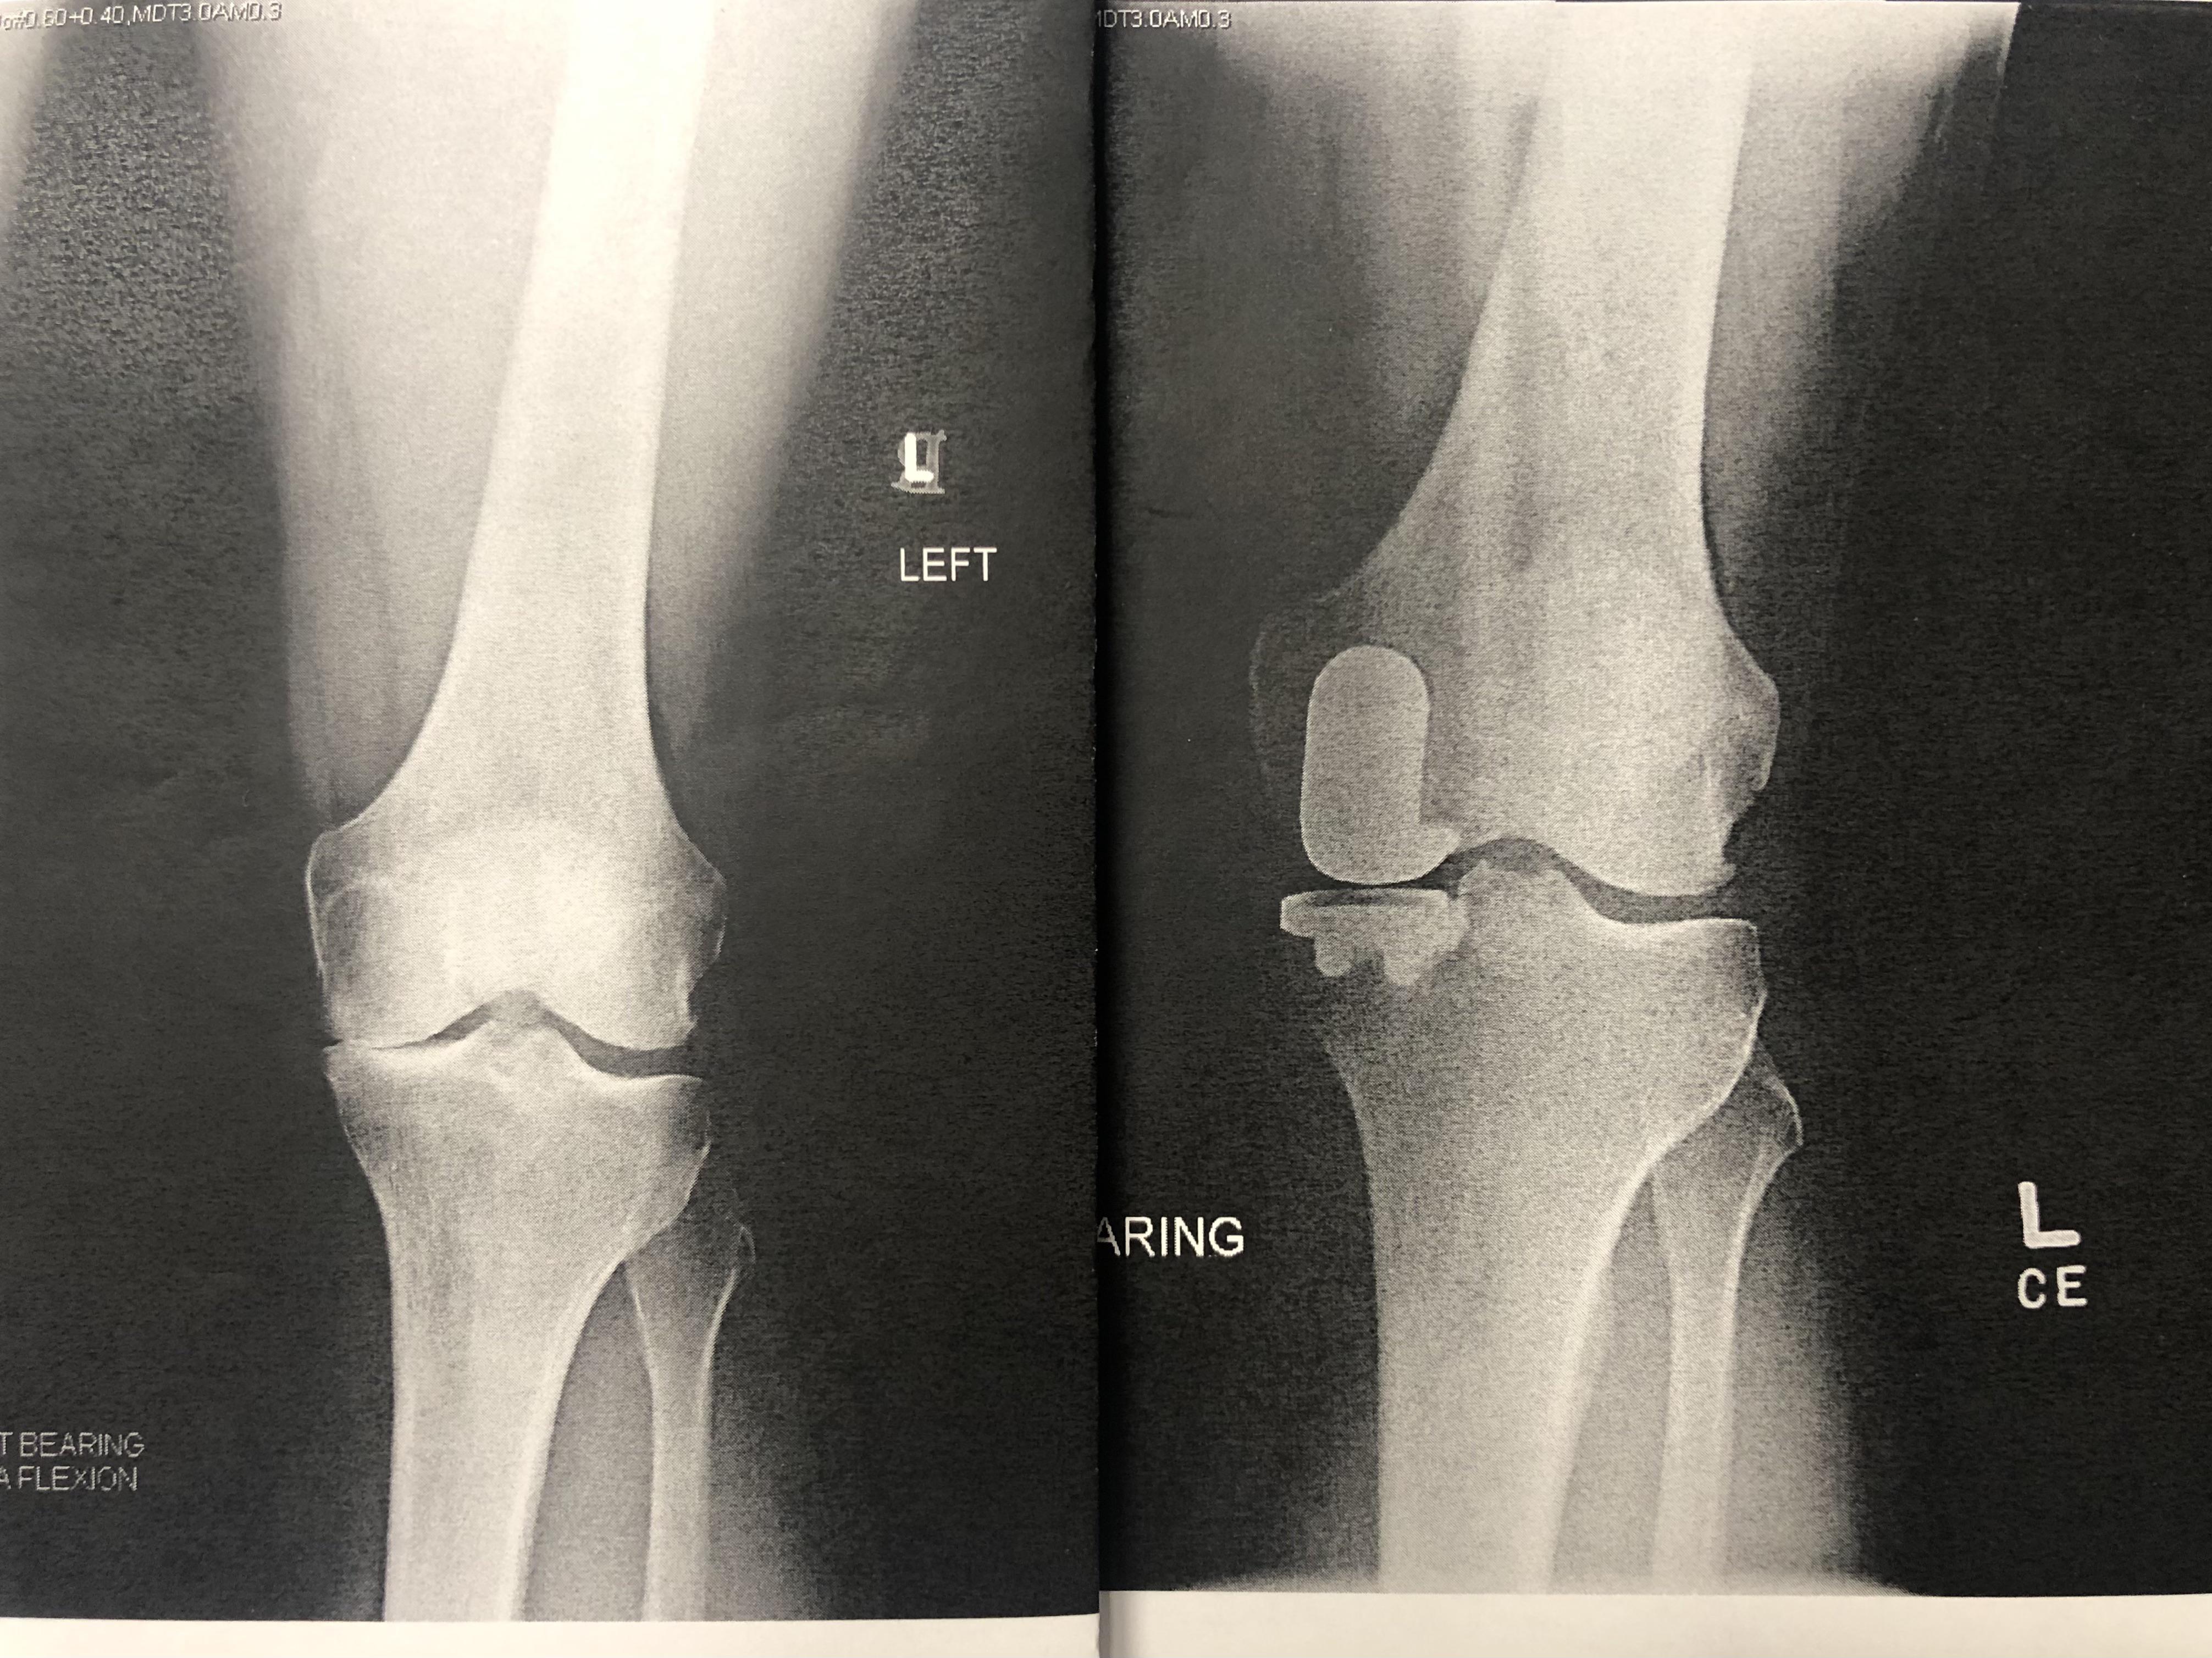

Before/After my partial knee replacement surgery. You can see the bone What Not To Do After Partial Knee Replacement Learn what types of activities can damage or delay the healing of your knee prosthesis after surgery. Learn how long it takes to recover from a partial knee replacement, also known as unicompartmental knee replacement, and what to expect at each stage. Learn about the benefits and risks of partial knee replacement, a surgical procedure that replaces only the damaged. What Not To Do After Partial Knee Replacement.